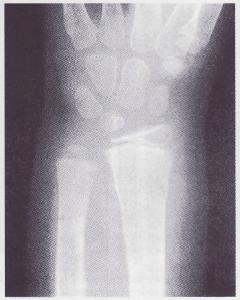

X線攝片,早期單純滑膜結核,可見骨質疏鬆和軟組織腫脹。尺橈骨下端結核可有死骨中心型和溶骨性破壞的邊緣型。晚期可見多個腕骨尺,橈下端和掌骨關節面廣泛破壞。腕關節出現畸形。

腕關節結核--X片①缺血性壞死:腕舟骨的缺血性壞死,也可顯腕部腫脹活動受限及壓痛,但其X線顯示受累骨密度增大,變形並有分節,晚期可呈不規則碎裂,有時可見囊性變,關節間隙一般不狹窄,也無骨破壞。

②類風濕性關節炎:可顯示骨質疏鬆,關節邊緣小囊狀缺損,關節間隙變窄,病理性半脫位,或骨性強直,但它常對稱性地累及多關節,其症狀間斷髮作,骨表面糜爛或呈小囊狀吸收,不會有膿腫、竇道或死骨形成。